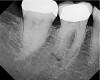

At this point, a diagnosis of previous endodontic therapy with a failing MB root in tooth No. 3 appears clear. But whether the cause of the patient’s chief complaint is this pathology or not requires further investigation. Because the patient complains of severe pain and increasing thermal sensitivity over the past few weeks, testing should be directed toward a diagnosis of a degenerating vital pulp and not a tooth with a history of endodontic treatment. Necrotic teeth or failing endodontically treated teeth do not manifest thermal sensitivity. This is why clinical tests, in combination with an emphasis on duplicating the patient’s chief complaint, are necessary to arrive at the correct diagnosis. After clinical tests are performed, tooth No. 30 is found to a have a severe, lingering response to the cold test and is slightly “different” to percussion. This test duplicates the patient’s chief complaint. Endodontic therapy in this tooth is performed and pain is relieved (Figure 3). Tooth No. 3, with its apical pathology around the MB root, is later retreated to address a missed second mesiobuccal canal (MB2), relieving the patient from the chewing pain (Figure 4).

Figure 4  Postoperative view of tooth No. 3.

Figure 4